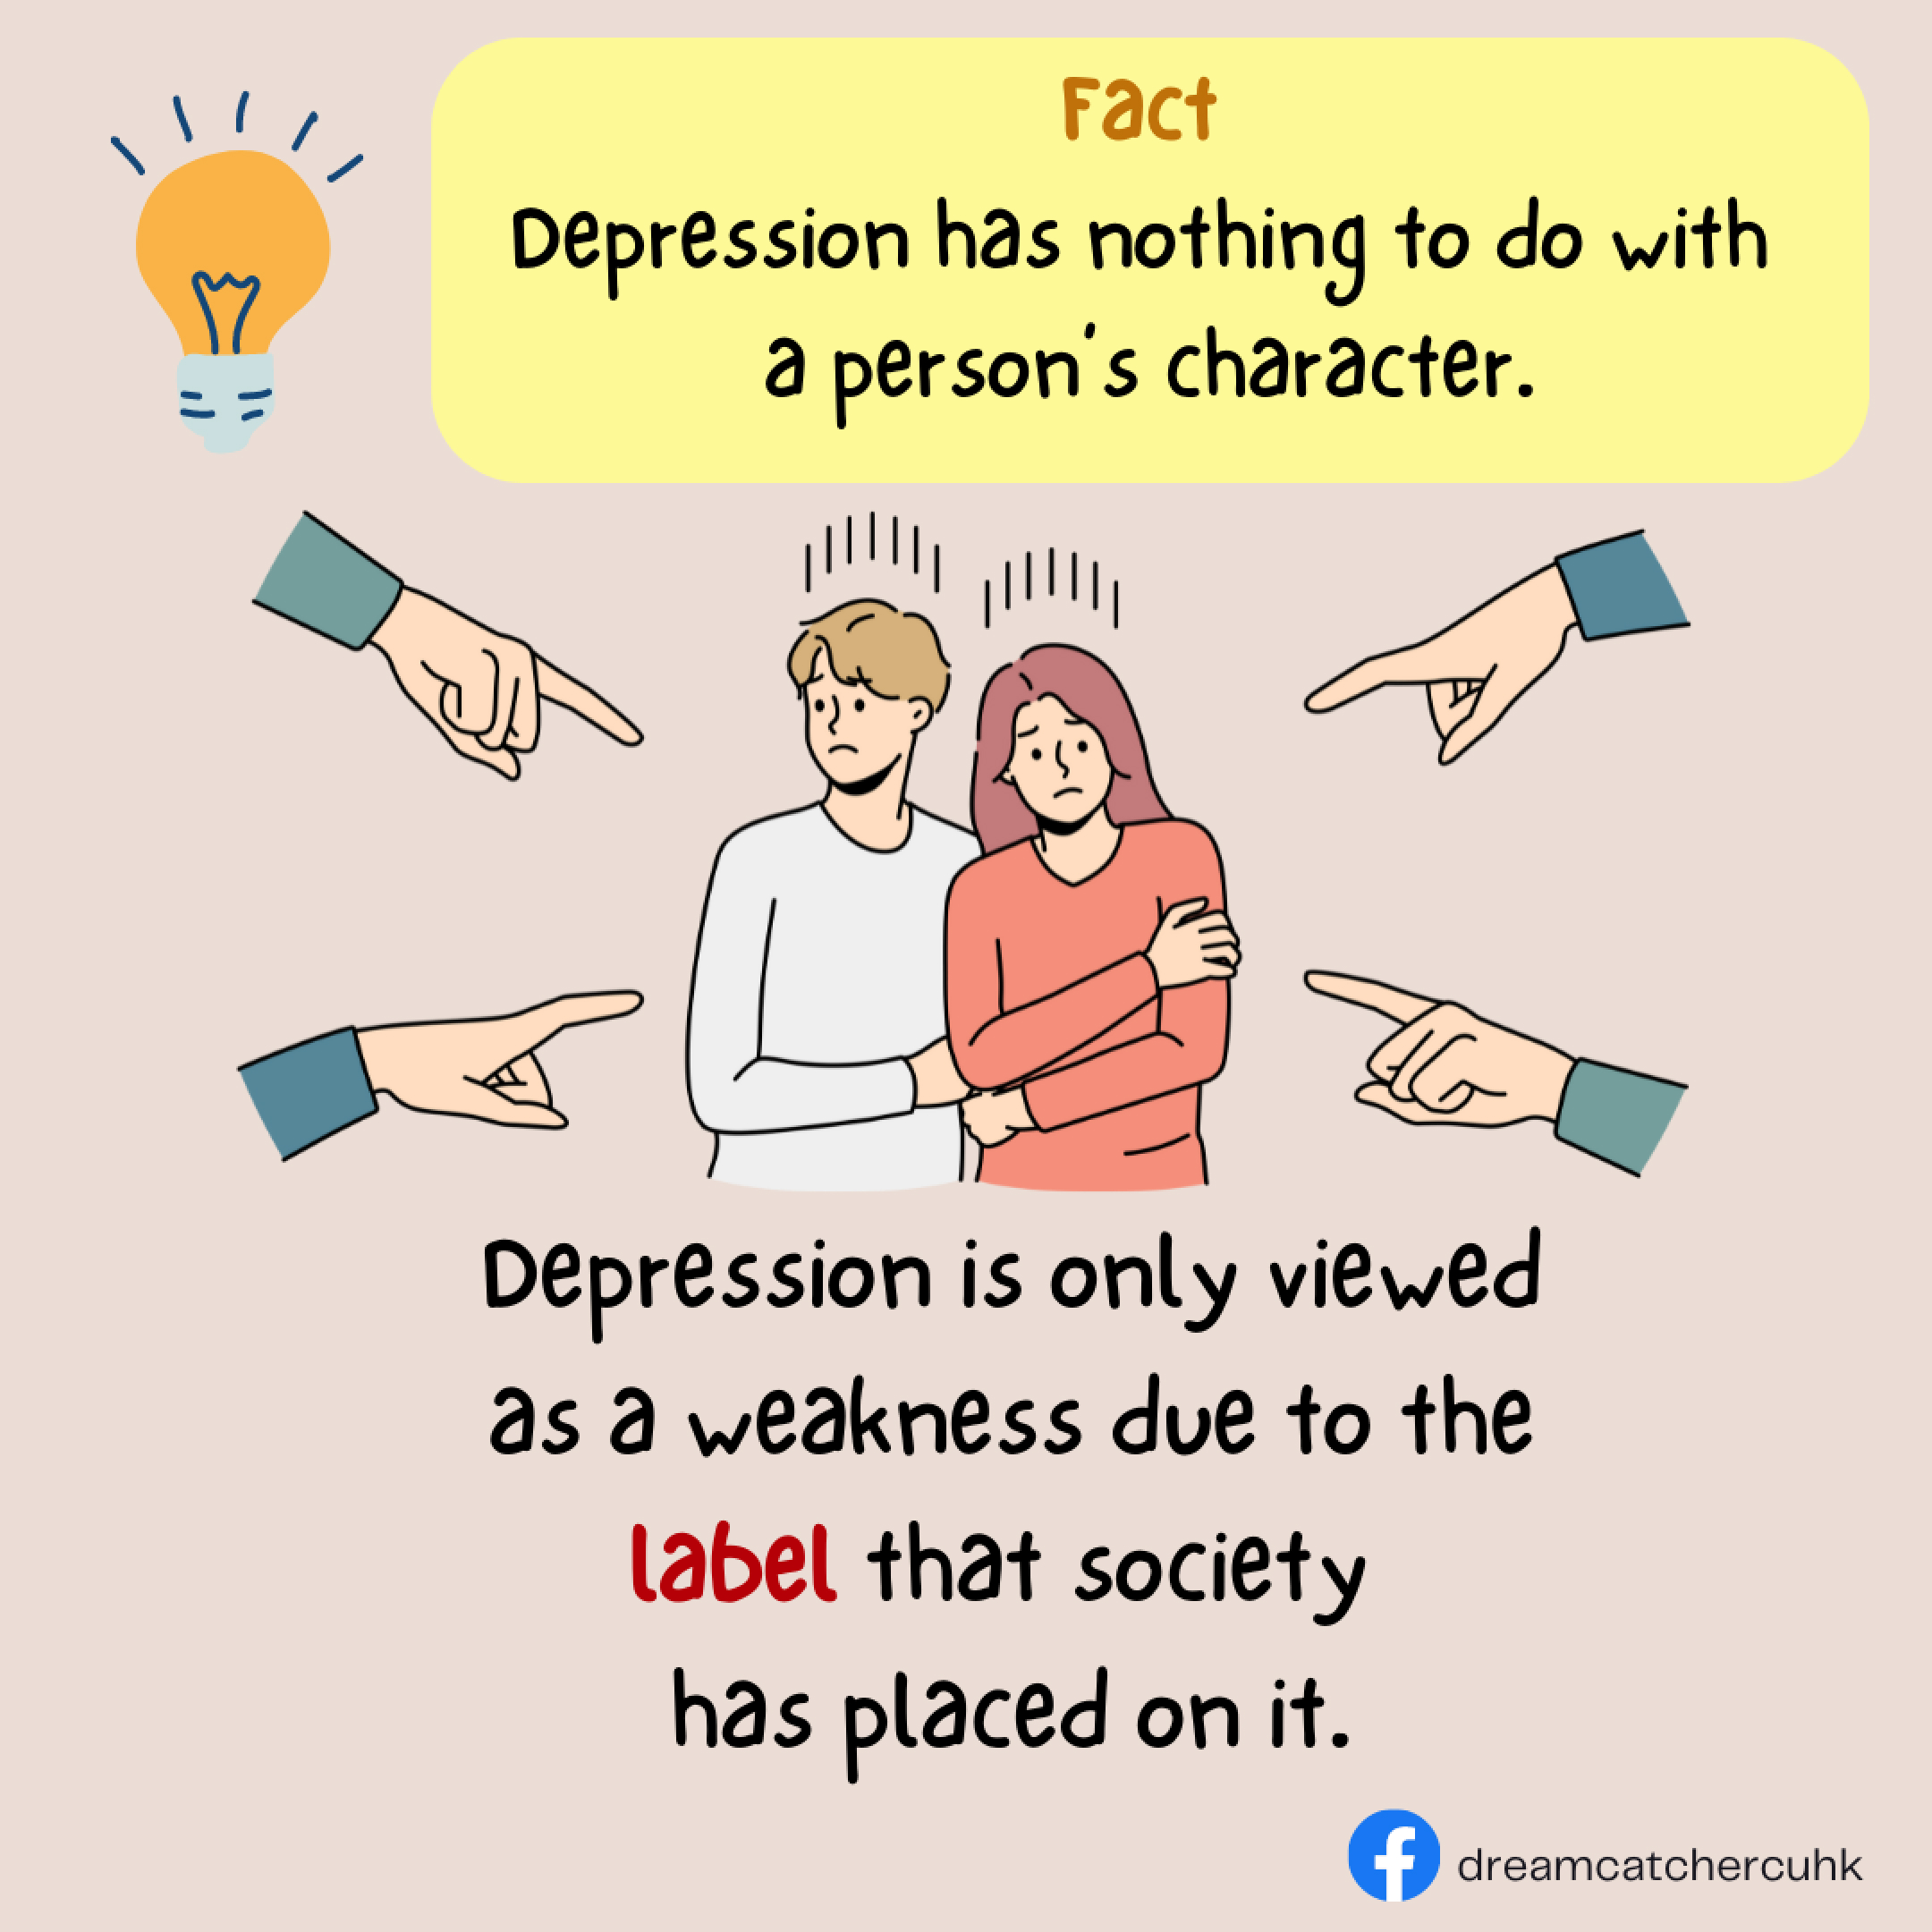

Mental Health